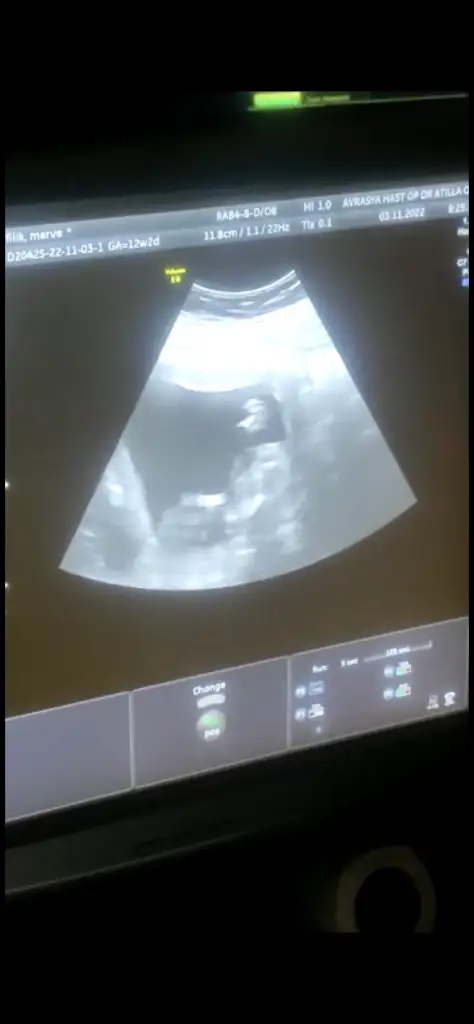

Kızlar 12+2 den merhaba bizde tahmin istiyoruzzz 🫶

• F2B00530-9F25-4CA7-AAC5-21CD09D4A420.webp

F2B00530-9F25-4CA7-AAC5-21CD09D4A420.webp

10 KB · Görüntüleme: 46